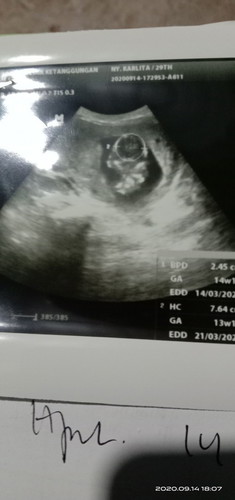

Dok,usia kandungan saya 14minggu.dan hasil USG kemarin katanya plasenta berada dibawah.apa itu tidak

Dok,usia kandungan saya 14munggu.tapi plasenta dibawah.apa gapapa dok?

bund...klo yg sya tau...plasenta dibawah yg biasa disebut plasenta previa itu ada bahaya ada jg tidak gmn kita menyikapinya... klo plasentanya menutup jalan lahir kemungkinan ga bs lahir normal...klo hanya disamping tp jalan lahir msh kebuka itu bisa lahir normal... hanya saja harus bedrest bund ga boleh terlalu cape atau banyak bawa beban berat karena bs perdarahan.... itu pengalaman sya dl waktu anal yg pertama diagnosanya plasenta previa

Baca lagibunda usg dimana? apa tidak dijelaskan bagaimana penanganan nya? ada beberapa kegiatan yg gaboleh di lakuin sm ibu hamil yg mengalami plasenta previa. coba bunda cek ke SpOG lain yg bs menjelaskan baik nya gmn

Saya waktu 16w plasentanya d bawah tapi sekarang udah normal lagi d 23w, kata dokternya itu kecapean makannya plasentanya d bawah tapi nanti naik sendiri.. Itu pengalaman sy s bun.